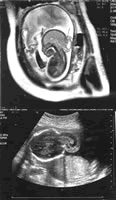

图1 枕部脑膜脑膨出MRI图像

矢状面,示枕部一混杂信号包块,内有呈高信号的脑脊液和呈等信号的脑组织通过局部颅骨的缺损与颅内相连。

图2 枕部脑膜脑膨出的轴面US图像, 百拇医药